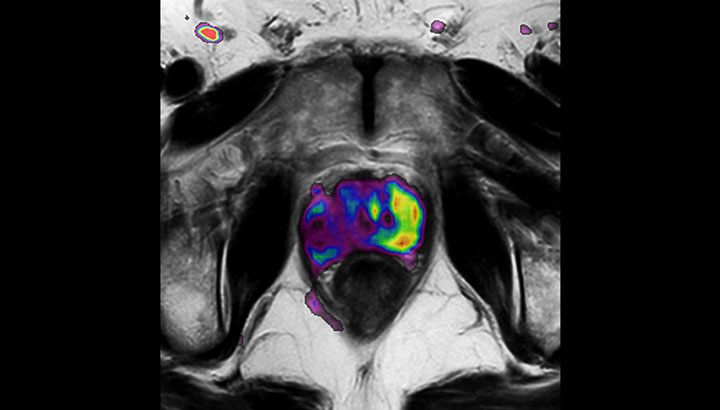

In addition to anatomical imaging, MRI offers the ability to obtain functional information that is beneficial for tumor detection and delineation, and for response monitoring.

Diffusion-weighted imaging (DWI) for example depicts areas of high signal intensity in soft tissues that are indicative of the restricted water mobility (i.e., diffusion) of a tumor and can also be used to identify lymph nodes. Changes in the tissue’s or lesion’s apparent diffusion coefficient (ADC) can provide insights that help predict the tumor’s response to radiotherapy. - No ionizing radiation